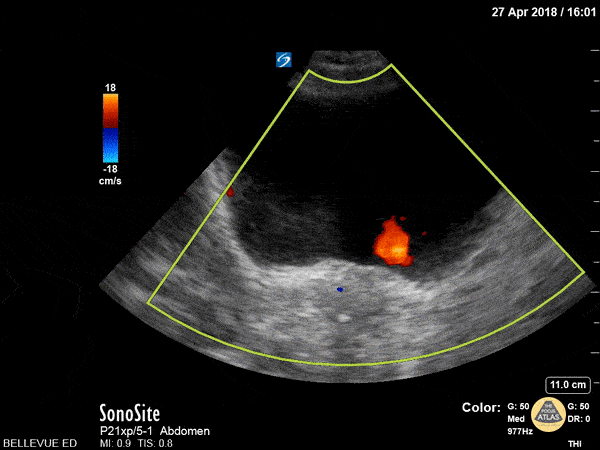

Renal/GU - UVJ Jets

This is a clip of the bladder in transverse view with visible ureteral jets. We can use color doppler to help visualize the jets of urine flowing out of the ureterovesical junctions into the bladder. In this case we see the red UVJ jets bilaterally from both ureters, ruling out obstruction proximal to the UVJ. Hannah Kopinksi and Dr. Lindsay Davis - NYU Emergency Medicine